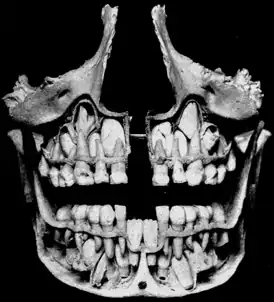

![]() Детский череп, постоянные зубы заменяют молочные. | |

Период сохранения молочных зубов и прорезывания постоянных называют периодом сменного прикуса — после выпадения молочного зуба до прорезывания постоянного обычно проходит 3-4 месяца. В дальнейшем последовательность смены зубов примерно соответствует прорезыванию молочных зубов. В возрасте 11 лет прорезываются вторые моляры. К 12-13 годам формируется постоянный прикус. Третьи моляры (зубы мудрости) прорезываются в возрасте 17—25 лет или позже либо вообще не прорезываются. У девочек прорезывание зубов происходит несколько раньше, чем у мальчиков.